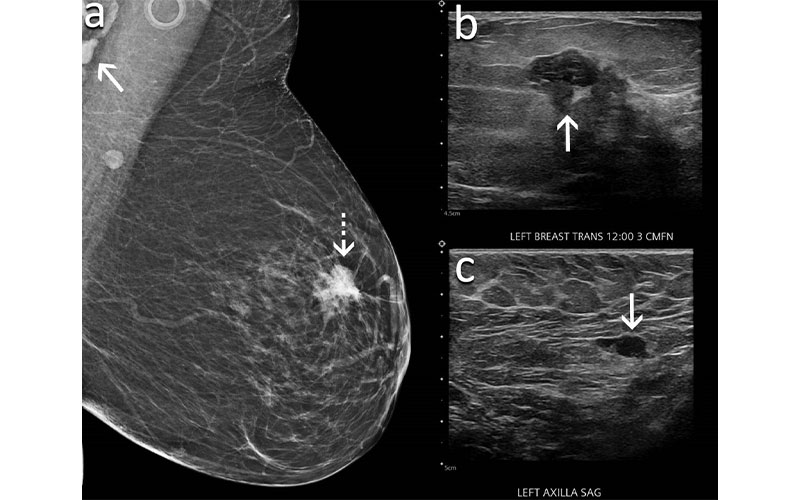

A 60-year-old woman presents for screening mammography nine weeks after receiving her second dose of the Moderna COVID-19 vaccine. (A) Mediolateral oblique view of the left breast demonstrates an irregular mass in the superior left breast (dash arrow) and a dense lymph node in the left axilla that is incompletely visualized (arrow). Sonography demonstrates (B) an irregular hypoechoic mass in the breast (arrow) that corresponded to the mammographic finding and (C) a lymph node with eccentric cortical thickening measuring 6 mm (arrow) in the axilla. Biopsy of the mass yielded invasive ductal carcinoma and biopsy of the lymph node yielded metastatic carcinoma.

Wolfson et al, Radiology 2022 ©RSNA 2022